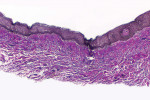

The histologic evaluation showed collagen that aligned horizontally, in a mostly parallel nature, to the superficial epithelium in both the ungrafted (Figure 10 and Figure 11) and grafted (Figure 12 through Figure 15) biopsy sites. In the grafted specimens, a clear demarcation at the interface of the native tissue and the implanted tissue was present. The implanted tissue, which was characterized by dense bands of disorganized collagen matrix, appeared well incorporated and without inflammatory cells. The Verhoeff's stain demonstrated the presence of numerous darkly stained elastin fibers in the implanted tissue that were inconspicuous in the native tissue.

The H&E and Verhoeff's stains allowed the collagen architecture of the native tissue to be clearly distinguished from that of the implanted tissue. The superficial native tissue exhibited collagen fibers that aligned parallel to each other and the epithelium, whereas the implanted tissue exhibited collagen fibers that appeared disordered. The implanted tissue, however, was markedly thicker than the overlying native tissue. Verhoeff's stain, which stains elastin fibers, has been used to identify implanted ADMs in grafted GRD sites.1,4,15 In this case, the abundant darkly stained elastin fibers in the grafted specimen indicate that the hydrated ADM was incorporated and not absorbed or exfoliated. The absence of observable inflammatory cells indicated that the implanted hydrated ADM was immunologically inert.